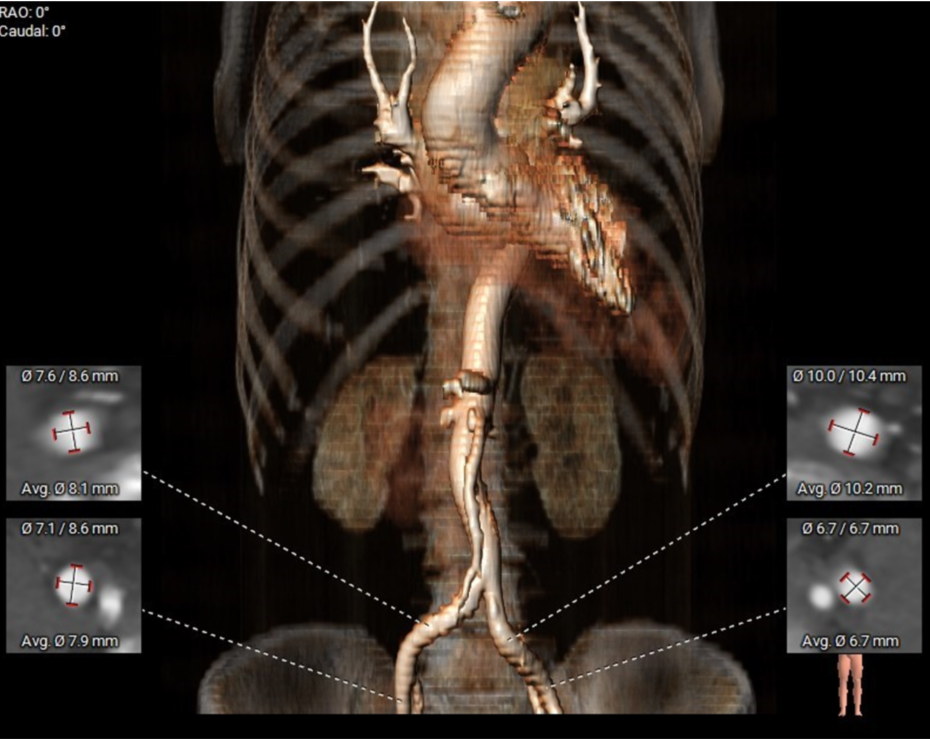

该患者为TYPE0型二叶瓣

主动脉根部CT测量数据

血管入路评估-主动脉弓为锐角弓,股动脉穿刺点血管径线良好